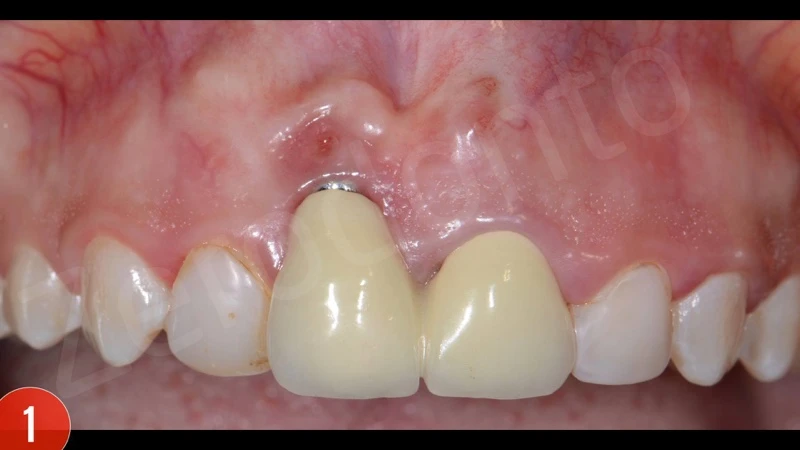

Người phụ nữ trẻ không hút thuốc có toàn thân khỏe mạnh đã được điều trị cấy ghép cho răng 11 và mong muốn che phủ sự thiếu hụt niêm mạc. Bệnh nhân phàn nàn là bị chảy máu và xuất hiện không thẩm mỹ. Bệnh nhân muốn duy trì implant cố định cũ.

Sau khi đánh giá X-quang ban đầu, các thành phần phục hình của cấy ghép implant đã không phù hợp, răng giả được nối liền. Ngoài ra, vị trí cấy ghép quá sâu. Chảy máu khi thăm khám dương tính.